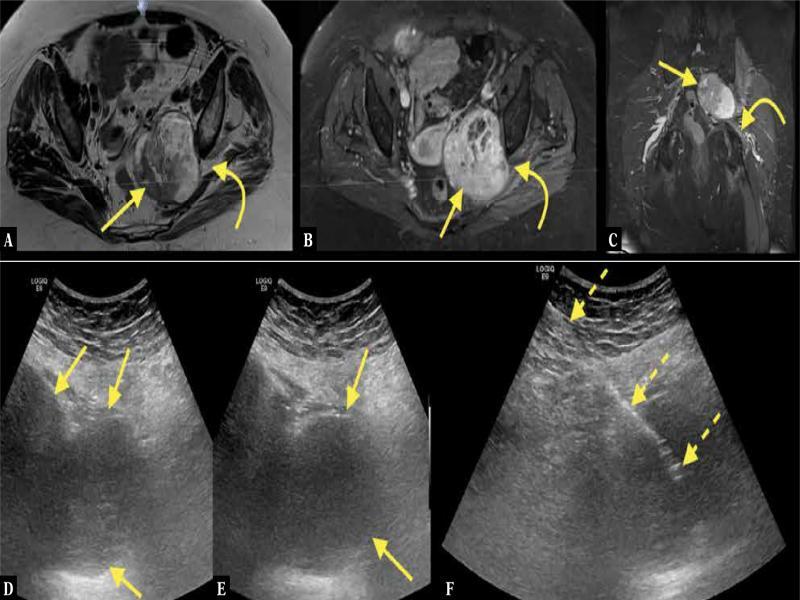

Fig. 9.

An 83-year-old patient with pain in the left buttock and leg. MRI of the pelvis with intravenous contrast revealed a tumor in the greater sciatic foramen ( A–C ; straight arrow – tumor, curved arrow – sciatic nerve). The MRI was unspecific; however, a diagnosis of malignant peripheral nerve sheath tumor was made because of the tumor’s direct relation to the sciatic nerve. The patient was referred for US-CNB ( D–F ; dashed arrows – biopsy needle). No histopathological diagnosis could be made. The patient was referred once again for US-CNB, where the histopathological diagnosis of benign peripheral nerve sheath tumor was made and confirmed after excisional biopsy